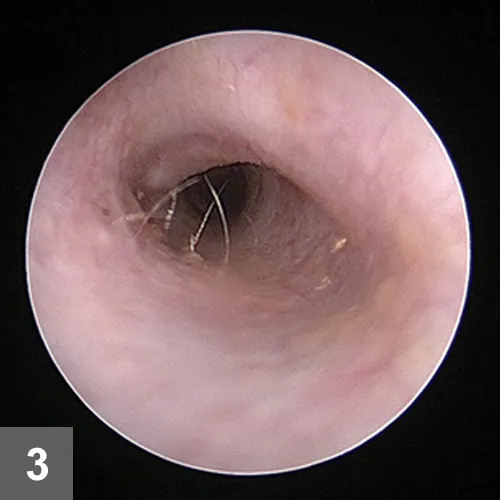

Figure 3. Eight weeks after initial presentation, the otitis externa had resolved and the tympanic membrane could be visualized.

At the second recheck, 8 weeks after initial presentation, Beignet’s pruritus score was 0. Mild hypotrichosis was present on the neck. The ears were nonpainful and pliable on palpation. The ear canals demonstrated scant erythema. Tympanic membranes were visualized and normal (Figure 3).